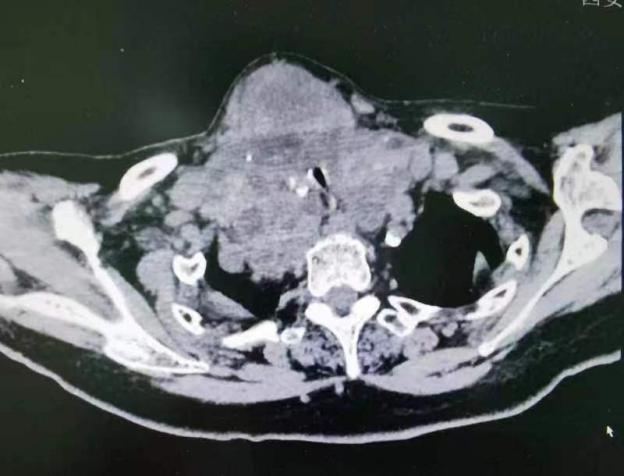

术前影像检查结果显示:气管受到严重压迫